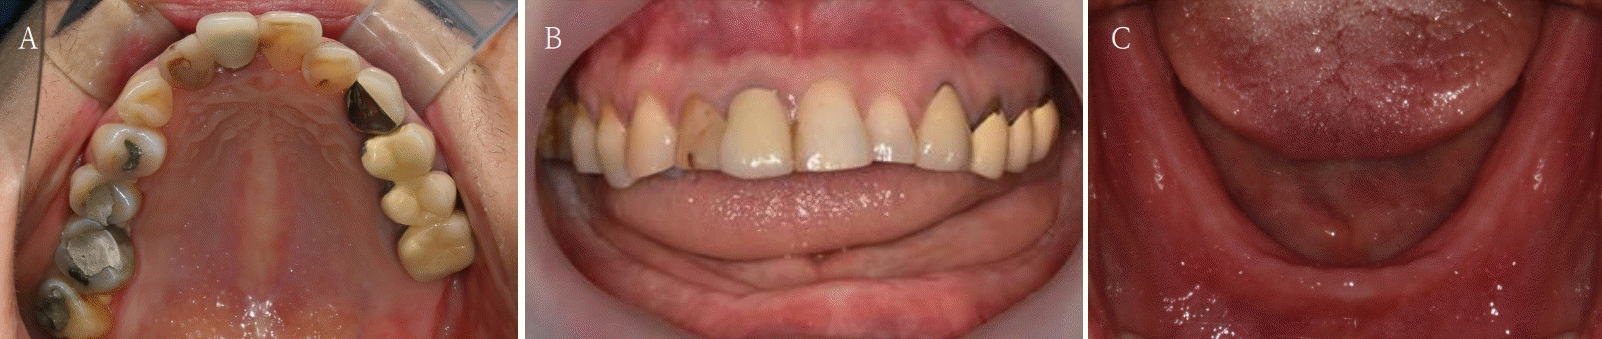

Fig. 1.

Atrophy of mandibular posterior bone is examined by pre-operative intraoral photograph. A. Maxillary occlusal view. B. Frontal view. C. Mandibular occlusal view.

본 증례는 44세 여환으로, 하악 의치가 계속 탈락하여 재제작을 원한다는 주소로 내원하였다. 상악은 고정성 수복물, 그리고 하악은 총의치를 착용 중이었고 하악 양측 구치부의 심한 골 흡수로 인해 유지력 소실로 불편감을 호소하였다. 3개월 전 하악 양측 견치를 발거한 이후로 하악 국소의치를 총의치로 전환하였고, 총의치는 구치부의 심한 교합면 마모와 의치의 후방부가 후구치 삼각 융기를 피개하지 않는 형태였다. 전신 병력으로는 지적장애 및 골관절염으로 약 2개월 간 약물 복용 중이었다. 상악 우측 제1대구치와 제2대구치, 제1소구치 그리고 제2소구치는 우식이 진행된 상태였고, 우측 제2소구치와 우측 제1대구치는 근관치료가 완료된 후 수복되지 않은 상태였다. 상악 좌측 제1소구치와 제2소구치, 그리고 제1대구치 수복물 하방으로 이차 우식이 진행된 상태였고, 전체적으로 교합평면이 균일하지 않은 형태였다(Figs. 1-3).상악 우측 구치부의 수복되지 않은 치아와 상악 좌측 보철물 하방의 이차 우식이 있는 치아는 모두 우식 제거가 필요하여 양측 구치부 각각 3개의 치아는 재수복을 결정하였고, 하악은 구치부의 심한 치조골 흡수로 인해 의치 사용은 불가할 것으로 판단하여 전방부에 임플란트를 식립하여 구치부는 캔틸레버 형태를 가지는 all-on-X 수복을 계획하였다. 의치의 수직고경에 맞춰 교합 평면을 균일하도록 하여 왁스업 시행하였고(Fig. 4), 이후 적절한 교합 수직 고경의 임시 의치를 제작하였다. 약 2개월의 적응기간을 거쳐 의치 적응도와 수직 교합 고경을 평가하였고 적절한 기능과 심미를 확인하였다. 상악 우측 제1소구치와 제2소구치, 제1대구치 그리고 상악 좌측 제1소구치와 제2소구치, 제1대구치는 우식을 제거한 다음, 임시 보철물로 재수복하여 적절한 교합 평면을 설정하였다(Fig. 5).환자가 적응한 임시 의치를 모델 스캔(Medit T710, Medit, Seoul, Korea)하여 프린팅용 레진(Graphy Tera Harz SG-100, Graphy, Seoul, Korea)을 이용하여 3D 프린팅하였고, 출력된 의치에 방사선 불투과성 레진(G-æenial Universal Flo, GC, Luzern, Swiss)을 부착하여 레진 마커를 형성하였다. 레진 마커를 부착한 프린팅 의치를 장착한 채로 콘빔 전산화 단층촬영(CBCT, R2 Studio Q, Megagen, Seoul, Korea)를 촬영하였다(Fig. 6). 촬영한 CBCT 데이터와 의치 스캔 파일을 중첩하여 CAD 소프트웨어(R2 Studio Q, Megagen, Seoul)를 통해 이상적인 임플란트 식립을 계획하였다. 전후방 거리를 연장하여 적절한 캔틸레버를 부여하기 위해 전방부에 3개의 임플란트를 식립하고, 양측 후방부에는 약 30도 경사진 임플란트를 식립하도록 계획하였다(Fig. 7).가이드는 상악의 자연 치열과 대합되는 의치 복제 형태의 상부 가이드, 그리고 가이드 핀이 존재하는 하부 가이드로 이루어지도록 디자인되었다(Fig. 8). 상부 가이드는 임시 의치의 스캔 데이터를 이용해 상부 가이드의 하부면과 하부 가이드의 상부면이 장착되어 구내에서 적합될 수 있도록 CAD 소프트웨어(Meshmixer, Autodesk, San Francisco, CA, USA) 상에서 디자인되었다. 임시 의치의 하부면과 하부가이드의 하부면을 치은과 중첩시켜 어버트먼트의 위치에 홀을 형성한 다음 3D 프린팅(Graphy Tera Harz SG-100, Graphy, Seoul, Korea) 하였다. 수술 당일 장착될 임시 보철물 또한 동일한 CAD 소프트웨어를 통해 제작하였다.수술 당일 이중 가이드를 구내에 장착하여 하부가이드를 고정 핀으로 고정시킨 후(Fig. 9), 계획된 위치에 임플란트 고정체를 식립하였다. 임플란트는 5개 모두 외부 연결형 고정체(AnyOne External, Megagen, Seoul, Korea)를 사용하였고, 식립 시 식립 토크는 모두 40N 이상, ISQ는 70이상으로 양호한 초기 고정력을 확보하였다(Fig. 10). 즉시 부하를 위해 기성 어버트먼트를 체결하였고, 임시 보철물을 장착하여 양측 소구치부에서의 균일한 교합을 확인하였다(Fig. 11).임플란트 주위 골과 치은의 회복을 위해 약 2달간 임시 보철물을 경과 관찰하였고, 이후 최종 보철을 위한 인상 채득을 시행하였다. 상하악 임시 보철물을 장착한 중심교합 상태에서 구내 스캔(Trios 4, 3 Shape, Copenhagen, Denmark)을 시행하여 악간 관계를 채득하였다(Fig. 12). 임시 보철물을 제거한 상태에서 하악의 전방부 3개의 임플란트에 scan body(Scan Abutment, Megagen, Seoul, Korea)를 연결하고, 양측 최후방 임플란트 2개에는 각각 Ti base multi-unit abutment(multi-angled abutment, Osstem, Seoul, South of Korea)를 30Ncm으로 체결한 후 multi scan body(TS Multi scanbody, Osstem, Seoul, Korea)를 연결하여 구내 스캔(Trios 4, 3Shape, Copenhagen, Denmark)을 시행하였다. 이후 스캔 바디를 연결하여 채득한 스캔 파일을 상하악 임시 보철물 상태에서 채득한 스캔 파일과 중첩하여 CAD 소프트웨어(exocad GmbH, Darmstadt, Germany)에서 최종 보철물을 디자인하였다(Fig. 13).최종 보철물은 양측 최후방 임플란트 고정체에 각각 Ti-base(TS multi Ti base, Osstem, Seoul, Korea)와 접착된 나사 유지형 단일 지르코니아 크라운으로, 지르코니아 블록(Zircen, Kuwotech, Gwangju, Korea)을 밀링하여 제작하였고, 치경부 하방으로 포세린으로 치은 형태를 부여하였다. 전방부 3개의 임플란트 고정체에는 맞춤형 지대주를 제작하여 30N으로 체결하였고, 양측 최후방 고정체는 20Ncm으로 체결한 후 레진 시멘트(Rely X U200; 3M ESPE, St. Paul, MN, USA)로 접착 시행하였다. 장착 후 중심교합시 양측의 제1대구치 부위에서 교합력이 적게 가해지도록 교합 조정 시행하였으며, 전방과 측방운동시에 임플란트 상호보호교합이 되도록 조정하였다. 또한 연결부 하방으로 치실을 통과시켜 치은 점막 사이 공간을 평가하였으며, 구강 위생 관리의 용이성을 확인하였다. 이후 1주, 1개월, 3개월 경과 관찰하였고, 환자는 저작이나 심미, 발음 등에서 만족해하였다(Figs. 14 and 15).